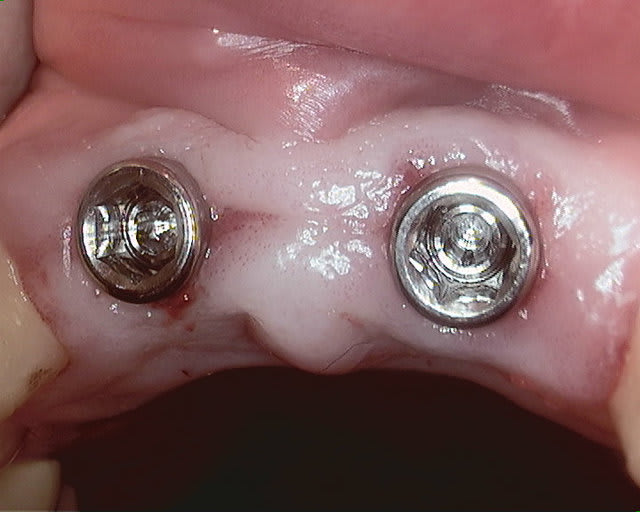

Merci pour le partage D57,

Je pense que le design de tes Axiom devraient être favorable à tes papilles par contre peut être que des piliers un peu plus anatomiques avec des provisoires préparés à l'avance avec un collage sur des capsules résines auraient facilité la suite mais je n'ai pas d'études ancestrales pour appuyer mes propos ni l'experience des membranes magiques

Une petite RX serait la bienvenue

et petite question métaphysique au passage :

est-ce que ce fameux bombé vestibulaire de la gencive est aussi primordial que cela dans les cas ou la gencive ne se découvre pas ?